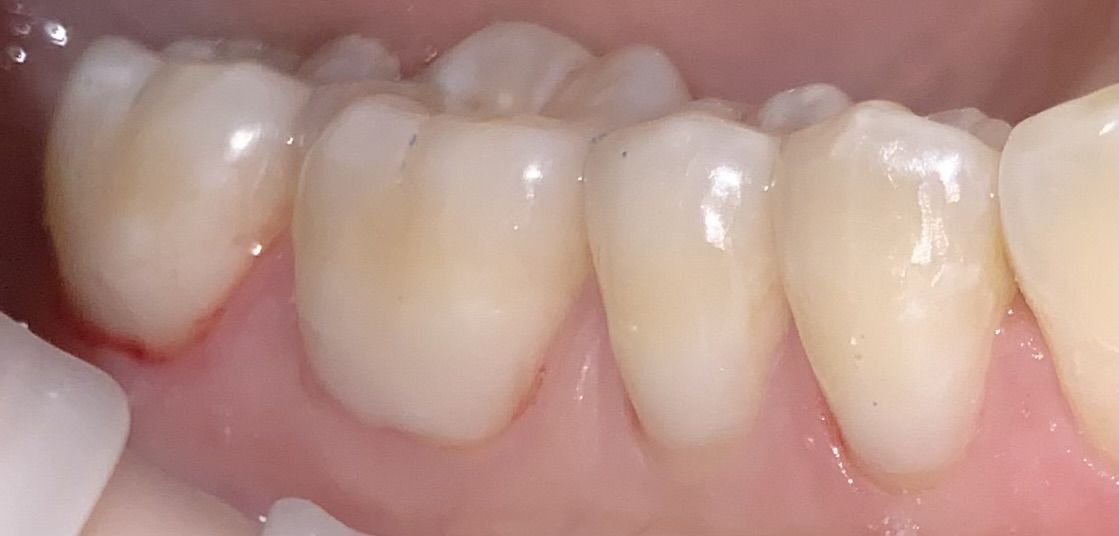

Before & After

Below are examples of the cosmetic outcomes that may be achieved with BPA-free gum coverings. Images are used with full patient consent. Individual results may vary.

Before

After